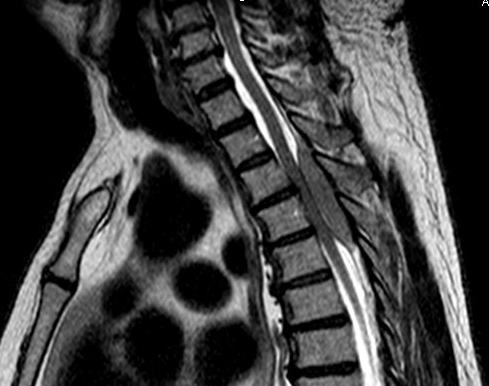

A 68 year old man with no significant past medical history presented with 3 weeks of upper back pain and bilateral leg weakness. He denied numbness, tingling, leg pain or urinary or fecal incontinence. MRI showed severe cord compression at the upper thoracic spine with a T2-T5 epidural mass. Due to the patient’s decline, an urgent decompression was scheduled and the patient underwent T2-T5 thoracic laminectamies with resection of extramedullary epidural tumor.

Imaging

Primary spinal epidural lymphoma (PSEL) includes extramedullary/extranodal lymphomas of the epidural space for which there are no other sites of disease at the time of diagnosis. As demonstrated in Figure 1 below, the lymphoma is seen entirely within the epidural space. 3

An epidural location for lymphoma is observed in 0.1-6.5% of cases. Patients tend to present in the fifth to seventh decade of life with a higher proportion of male to female cases. Presenting symptoms include weakness in the upper or lower limbs and back pain corresponding to the site of involvement of tumor. The most common tumor site is the thoracic spine (75%) followed by lumbar and cervical. Most epidural spinal tumors are B-cell lymphomas of intermediate and high grade, but low grade lymphomas have been reported. 3